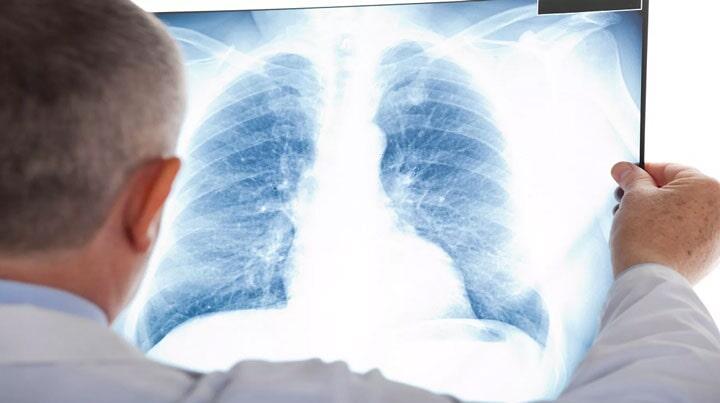

Rehabilitación

pulmonar

La rehabilitación

pulmonar se realiza en todos aquellos pacientes que presenten alguna

enfermedad que se acompañe del mal manejo de secreciones

bronquiales higiene bronquial y oxigenación adecuada permitiendo que el

paciente se encuentre en un estado de confort.